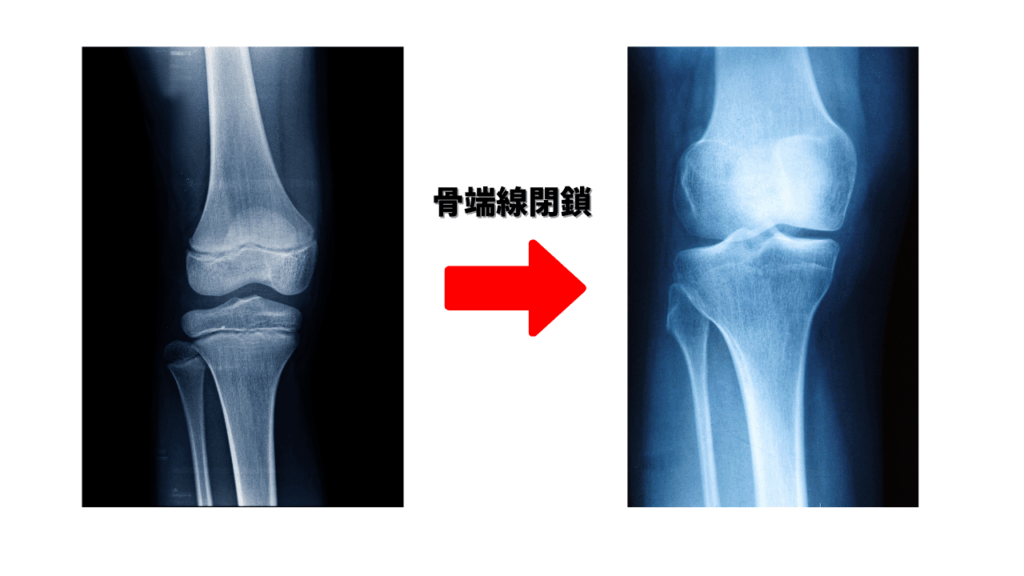

第3章:骨端線閉鎖:成長の終わりと診断

思春期に分泌される性ホルモンが、骨端線の軟骨細胞の活動を停止させ、骨化を加速することで骨端線閉鎖が起こります。骨端線が閉鎖すると、身長の伸びは完了します。

閉鎖時期は個人差が大きいですが、一般的に女子が14〜16歳頃、男子が16〜18歳頃が目安です。

3-2. 骨端線の診断方法

- X線(レントゲン)検査: 手の骨を撮影し、骨の成熟度合いを示す骨年齢を算出し、成長の残りの余地を予測します。